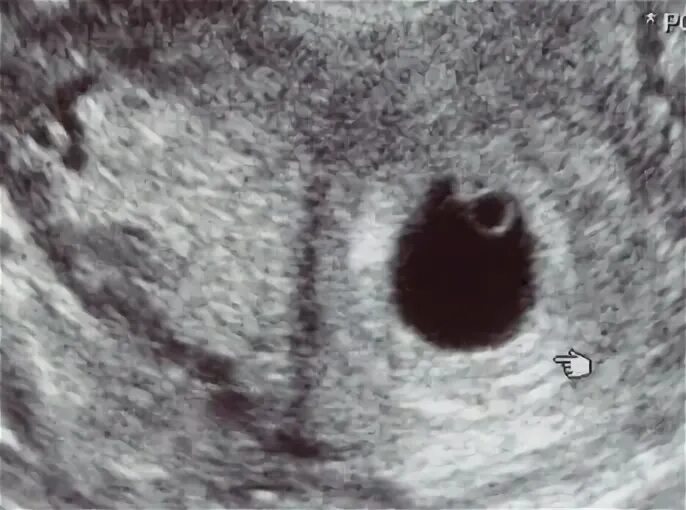

Желточный мешок 2 мм